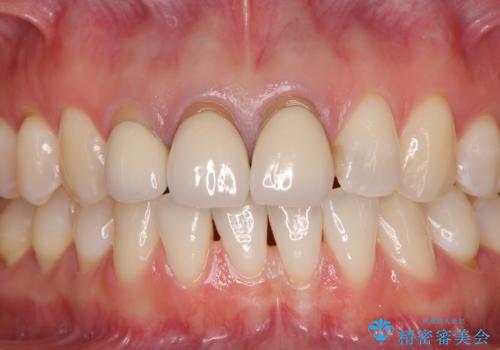

- 上の前歯のセラミッククラウンが古くなったことと、下の前歯のデコボコを気にして来院された患者様です。

前歯は一部根管治療を行った後にオールセラミッククラウンに補綴することとしました。

補綴治療に先立ち、下顎前歯の部分矯正を行い、前歯の咬み合わせの安定性向上を図りました。